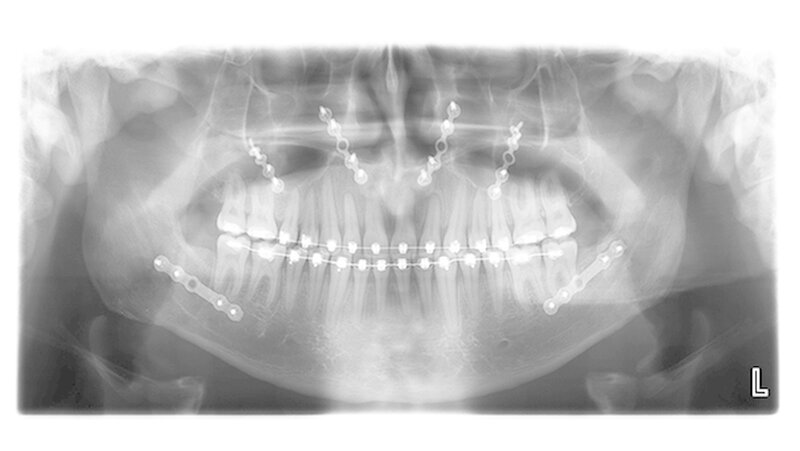

Die Abbildungen 1 und 2 zeigen die klinische Situation bei Erstvorstellung: Der Unterkiefer ist zu prominent. Der Oberkiefer und das Mittelgesicht liegen zurück. In der Front liegt ein umgekehrter Überbiss vor. Der Unterkiefer steht vor dem Oberkiefer. Das erschwert das Abbeißen und Kauen der Nahrung. Die Scans (siehe Abbildungen) dokumentieren, wie aufwendig die virtuelle Operationsplanung erfolgen musste.

Nun muss die Biss-Situation anhand des Computer gefertigten Biss-Schlüssels exakt eingestellt werden, bevor mit zwei Millimeter dicken Osteosyntheseplatten aus Titan der Knochen in der neuen Position mit Hilfe von Titanschrauben fixiert wird. Im Unterkiefer erfolgt die Schnittführung im Zahnfleisch hinter dem letzten Backenzahn beidseits. Nun wird der Unterkiefer mit spezieller Technik durchtrennt. Dies erlaubt eine Verschiebung der Zahn tragenden Basis vom Gelenk tragenden Knochenabschnitt des Unterkiefers.

Bei der Präparation wird der im Unterkieferknochen verlaufende Nervus alveolaris sorgfältig geschont. Die neue Position wird mit einem zweiten Biss-Schlüssel, der die endgültige Biss-Situation einstellt, zugeordnet und mit Osteosyntheseplatten und -schrauben gesichert.

Die Platten und Schrauben fixieren den Knochen in der Art und Weise, dass der Patient postoperativ weiche Kost essen darf. Nach einer Woche werden die Fäden entfernt, die kieferorthopädische Feineinstellungdes Bisses kann jetzt beginnen.